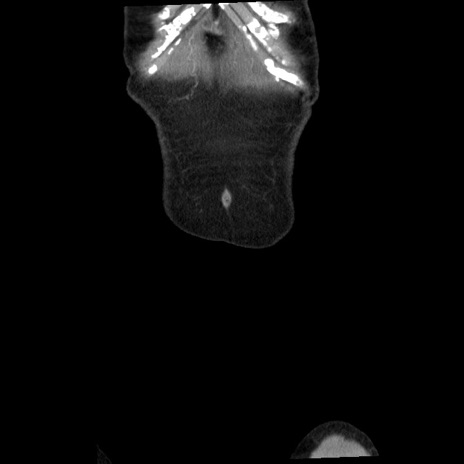

症例1(冠状断像)

症例

【症例】80歳代女性

【主訴】腹痛

【現病歴】8時間前から腹痛あり来院。

【既往歴】糖尿病、脂質異常症、子宮体癌にて子宮全摘術

【身体所見】意識清明・会話良好だが腹痛で苦悶様、全腹部にわたって反跳痛と圧痛あり

【データ】WBC 13600、CRP 0.14、LDH 224、CK 90